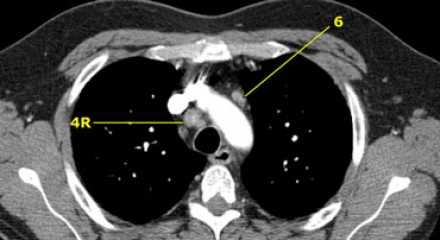

На изображении слева 3А узел в преваскулярном пространстве. Обратите внимание так же на ниже расположенные паратрахеальные узлы справа относящиеся к 4R группе.

4R. Правые нижние паратрахеальные лимфатические узлы

- Верхняя граница: пересечение нижнего края левой плечеголовной вены с трахеей.

- Нижняя граница: нижний края непарной вены. 4R узлы распространяются до левого края трахеи.

На изображении слева мы видим 4R паратрахеальные узлы. Кроме того здесь представлен узел кнаружи от дуги аорты, то есть 6 группы.

4L. Левые нижние паратрахеальные лимфатические узлы

4L узлы расположенные слева от левой стенки трахеи, между горизонтальными линиями проведенными касательно верхней стенке дуги аорты и линией проходящей через левый главный бронх на уровне верхнего края верхнедолевого бронха. Они включают паратрахеальные узлы расположенные кнутри от артериальной связки.

Узлы 5 группы (аортопульмонального окна) расположены кнаружи от артериальной связки.

На левом изображении над уровнем легочного ствола представлены нижние паратрахеальные узлы слева и справа, так же здесь представлены узлы 3 и 5 групп.

Изображение слева выше уровня карины. Слева от трахеи 4L узлы. Обратите внимание что они расположены между легочным стволом и аортой, но не в аортопульмональном окне, потому что они лежат медиальнее артериальной связки. Лимфатические узлы латеральнее легочного ствола относятся к 5 группе.